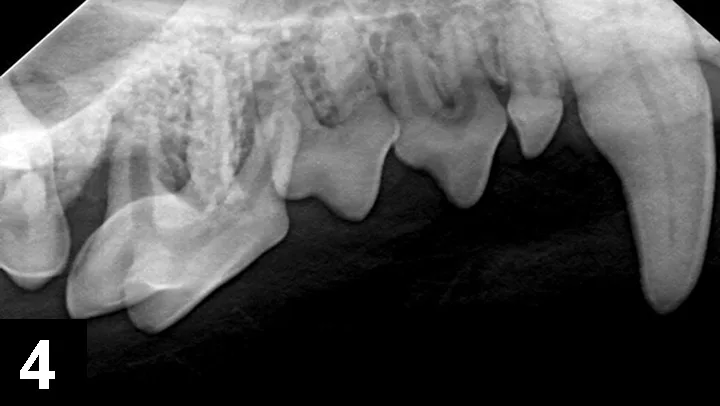

Approximately 25% of dogs are presented with one or more fractured teeth, and 10% have a complicated crown fracture indicating the pulp canal is exposed (Figure 1).4-6 Once exposed to the oral cavity, the canal pulp becomes contaminated, infected, and necrotic, eventually resulting in periapical infection and pain. An oral examination of the patient while under general anesthesia can detect exposed canal pulp; a dental explorer will stick or drop into the open pulp. If open pulp is identified, intraoral radiographs are required to assess the periapical tissues (eg, periapical lucency, root resorption) and the size of the pulp canal (eg, may be wider compared to the contralateral tooth; Figure 2). Necessary treatment options for a pulp-exposed, infected tooth include root canal treatment or surgical extraction.

Left mandibular canine tooth root (tooth 304) that had a complicated crown fracture. A periapical lucency, external inflammatory apical root resorption, and a relatively widened pulp canal are present, indicating the tooth has been dead and infected for months. The chronically exposed pulp results in periapical infection and inflammation.